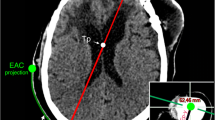

A total of 10 catheter implantations were performed in human cadaver specimens. All catheters were implanted in the frontal horns of lateral ventricles in the first attempt leading to a 100% first pass success rate. The 3D Euclidean error (3D distance) between the software-planned and the frame-targeted coordinates was 1.8 ± 0.6 mm (n = 10, Fig. 3J). We also measured the deviation of the catheter from its trajectory in the XY plane of the target and referred to it as the trajectory error. The trajectory error was found to be 1.9 ± 0.8 mm (n = 10, Fig. 3J). The distance of the margin of catheter tip from the FOM was found to be 3.9 ± 1.6 mm (n = 10). The average time taken for key placement, surgical planning (including fiducial registration), and EVD implantation was 1.6 ± 0.4 min (n = 4), 9.4 ± 3.5 min (n = 10), and 14.7 ± 2.6 min (n = 8) min, respectively (Fig. 3K). Two observations for implantation time were excluded as they employed a pre-existing burr hole. The total time for the procedure excluding the CT scan was 26.5 ± 3.1 min per implant (n = 8, Fig. 3K). Figure 4 shows the targeting accuracy assessment of a representative experiment by superimposing the planned trajectory on the actual trajectory using COMPASS surgical planning software (COMPASS International Innovations, Rochester, MN). The entire procedure was completed on the CT scanner table without transporting the specimen.

CT images showing robust targeting accuracy in a representative pre-clinical experiment (COMPASS software). The actual location of catheter tip (red circle) is seen to be overlying the planned location (blue dot). The bottom right panel shows the actual catheter trajectory (white glow) with superimposed planned trajectory (red line). Cerebral vasculature was avoided while placing the catheter.

The catheter tip was located within ipsilateral frontal horn in all implantations and thus judged Grade I (optimal/adequate) as per Kakarla et al.'s clinical grading system1 (supplementary Table S1). For 9 implantations, the catheter tip was located within 5 mm of ipsilateral FOM and judged as ideal based on Fargen et al.’s4 grading system (supplementary Table S2). For one implantation, the tip was placed 8 mm from the FOM in the ipsilateral lateral ventricle and judged as acceptable. For experiments emulating surgical planning with CTA, a thorough visual inspection of the post-procedure CT images revealed no direct contact of the catheter with visible vessels (n = 5, see Fig. 4, bottom right panel for representative image).

The EVD key and localizer were secured on the back half of the cadaver head with two midline pins and two side screws (Figs. 3B, 1C). The anterior pin was placed 17–18 cm behind the nasion in the midline. The specimen was imaged in a CT scanner with a slice thickness of 0.6 mm (Fig. 3C). The images were transferred to a surgical planning computer. COMPASS software was used for fiducial registration and surgical planning. A target in the frontal horn of lateral ventricles (Fig. 3D) and a trajectory which avoids the eloquent cortex as well as CT visible vasculature were chosen. The software provided the coordinates for the target, X, Y and Z value, as well as the trajectory, arc and collar angles.

The X, Z, arc, and collar values of the surgical target were dialed into the stereotactic device (Fig. 3E) and it was locked on the EVD key at the designated Y coordinate. The site for incision was marked (Fig. 3F) followed by scalp incision and stereotactic drilling of a 5 mm diameter burr hole (Fig. 3G). The dura was punctured with a sharp needle. A metal catheter was then advanced to the target and secured in place (Fig. 3H). A post-procedure CT scan was performed to verify the catheter coordinates and trajectory using COMPASS. To account for errors involved in the frame placement and registration and in having different head shapes, all surgical steps right from the EVD key and localizer placement to the post procedure CT scans were repeated multiple times and on multiple cadaver heads. All steps were performed by a post-doctoral fellow who completed medical school training and has prior experience in cadaveric stereotactic procedures.

The first attempt success rate, targeting error (3D Euclidean error), trajectory error, catheter tip location from FOM, number of blood vessels in contact with the catheter (radiographic assessment), and surgical time were assessed and documented. The location of catheter tip on the post-procedure CT scan was evaluated as per the clinical grading systems given by Kakarla et al.1 and Fargen et al.4.